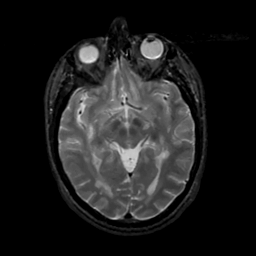

MR Study #8, March 31, 1991 -- Slice #22